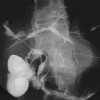

Alo Dokter. Saya memiliki pasien, perempuan 78 tahun. Hasil USG menunjukan lesi hiperekoik di duktus hepatikus communis dengan diameter 0.9cm dan tampak dilatasi ringan pada duktus intrahepatik kanan-kiri. Pasien tidak memiliki keluhan nyeri perut ataupun ikterik. Pasien memiliki riwayat post mrm ca mammae 4 tahun lalu dan daat ini rutin minum tamoxifen. Apakah pasien boleh diberikan asam ursodeoksikolat? Terimakasih